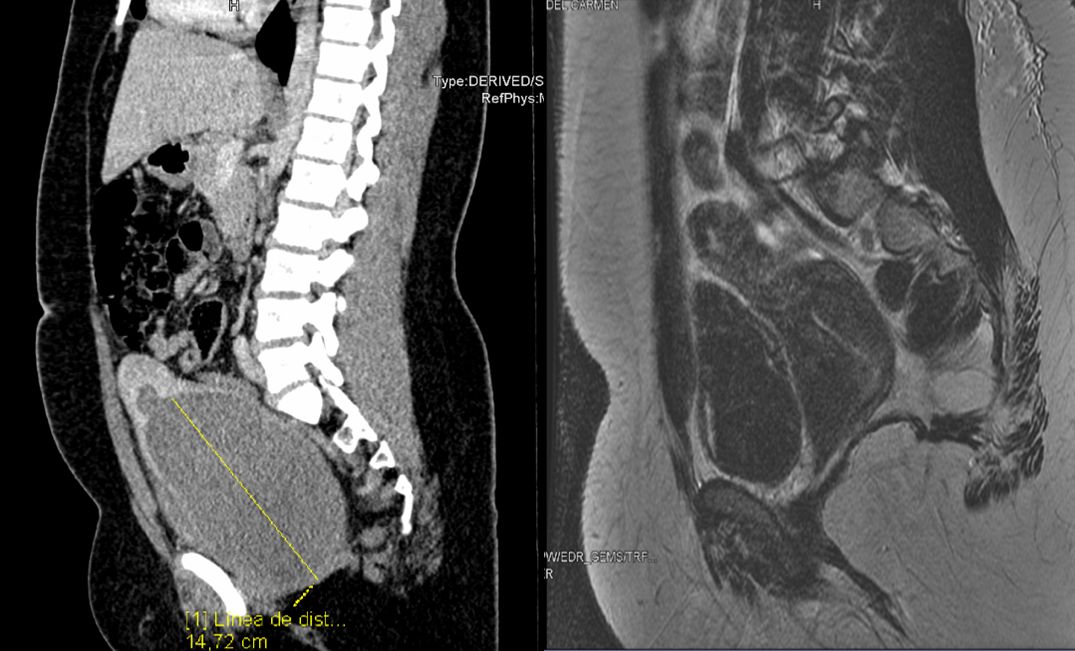

En el TAC urgente que se solicitó se evidenció un útero dilatado de hasta 15x10x10 cm con contenido hetereogéneo compatible con hemartros y una morfología bicorne (Figura 1). Ante la sospecha de malformación uterina se realizó drenaje vía transvaginal bajo sedación con extracción de un litro de contenido hemático y se inició tratamiento con anovulatorios para evitar menstruaciones.

Se completó estudio con resonancia magnética (RM) pélvica en la cual se evidenció una hipertrofia compensadora del riñón derecho en probable relación con la agenesia renal izquierda ya conocida y dos cavidades uterinas sin comunicación entre ambas compatible con un útero doble o didelfo (Fig. 1). El cérvix del hemiútero derecho, de morfología normal, se encontraba lateralizado hacía la derecha, y el del hemiútero izquierdo se encontraba distendido con alteración en su morfología compatible con hematrometra y hematocolpos de la hemivagina ipsilateral obstruida.

| Figura 1. Tomografía computarizada (a la izquierda) y resonancia magnética (a la derecha) de la paciente |